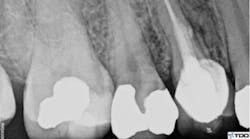

A clinical exam confirmed the presence of a draining sinus tract. Periodontal probing depths were within normal limits, and the restoration was intact. The radiograph showed previous root canal therapy, post, and crown. A radiographic exam revealed a radiolucent area on the mesial aspect of tooth No. 5 in the coronal third adjacent to the post, as well as a periradicular radiolucency (figure 1).

Figure 1: Radiolucent area on mesial aspect of Tooth No. 5 in coronal third adjacent to post, as well as a periradicular radiolucency